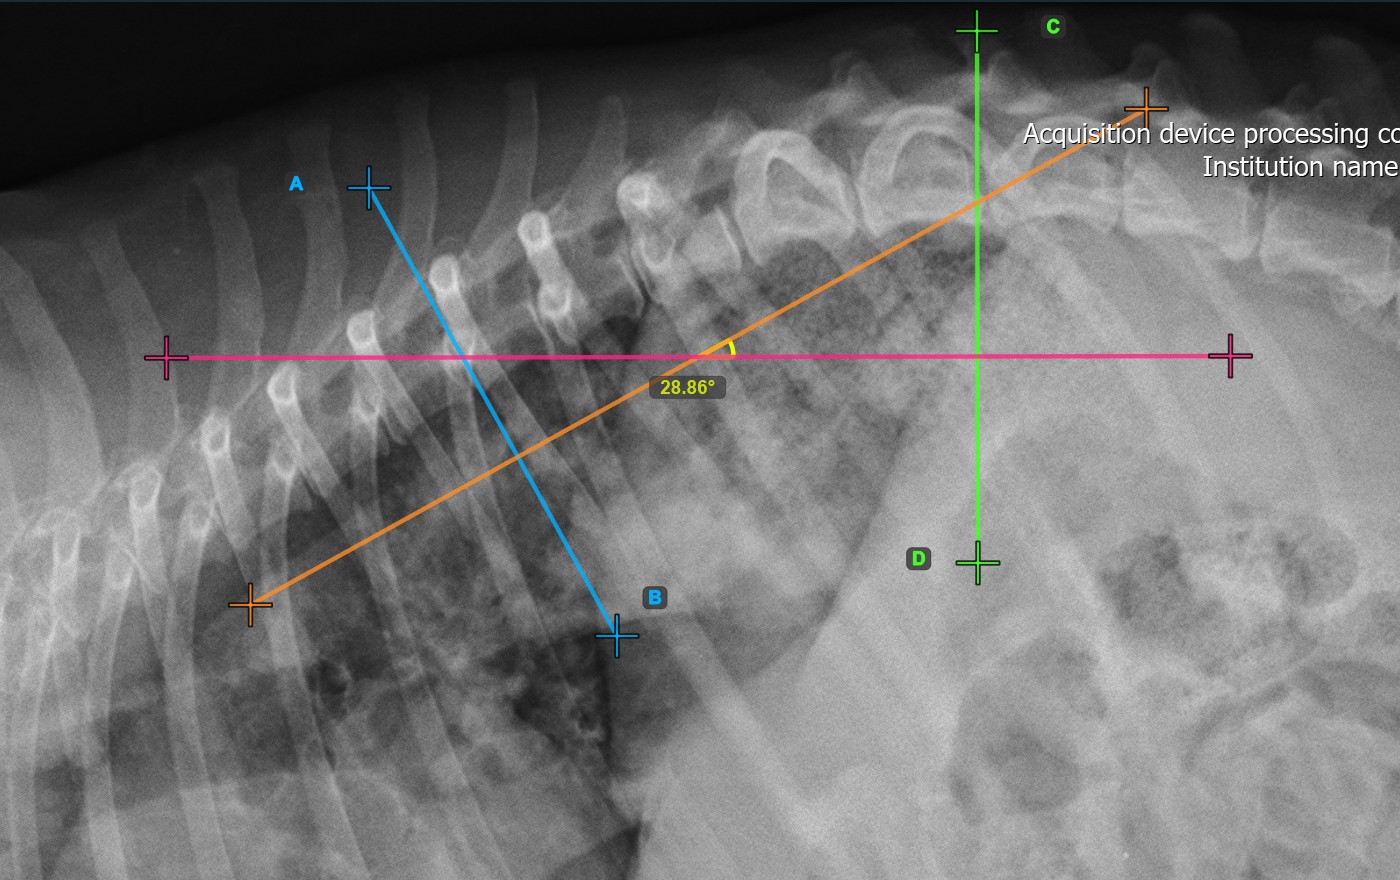

The image below represents a typical placement of the second vertebral line.

../../_images/image374.jpg

Modify the position and orientation of the two vertebral lines to automatically recalculate the Cobb Angle.